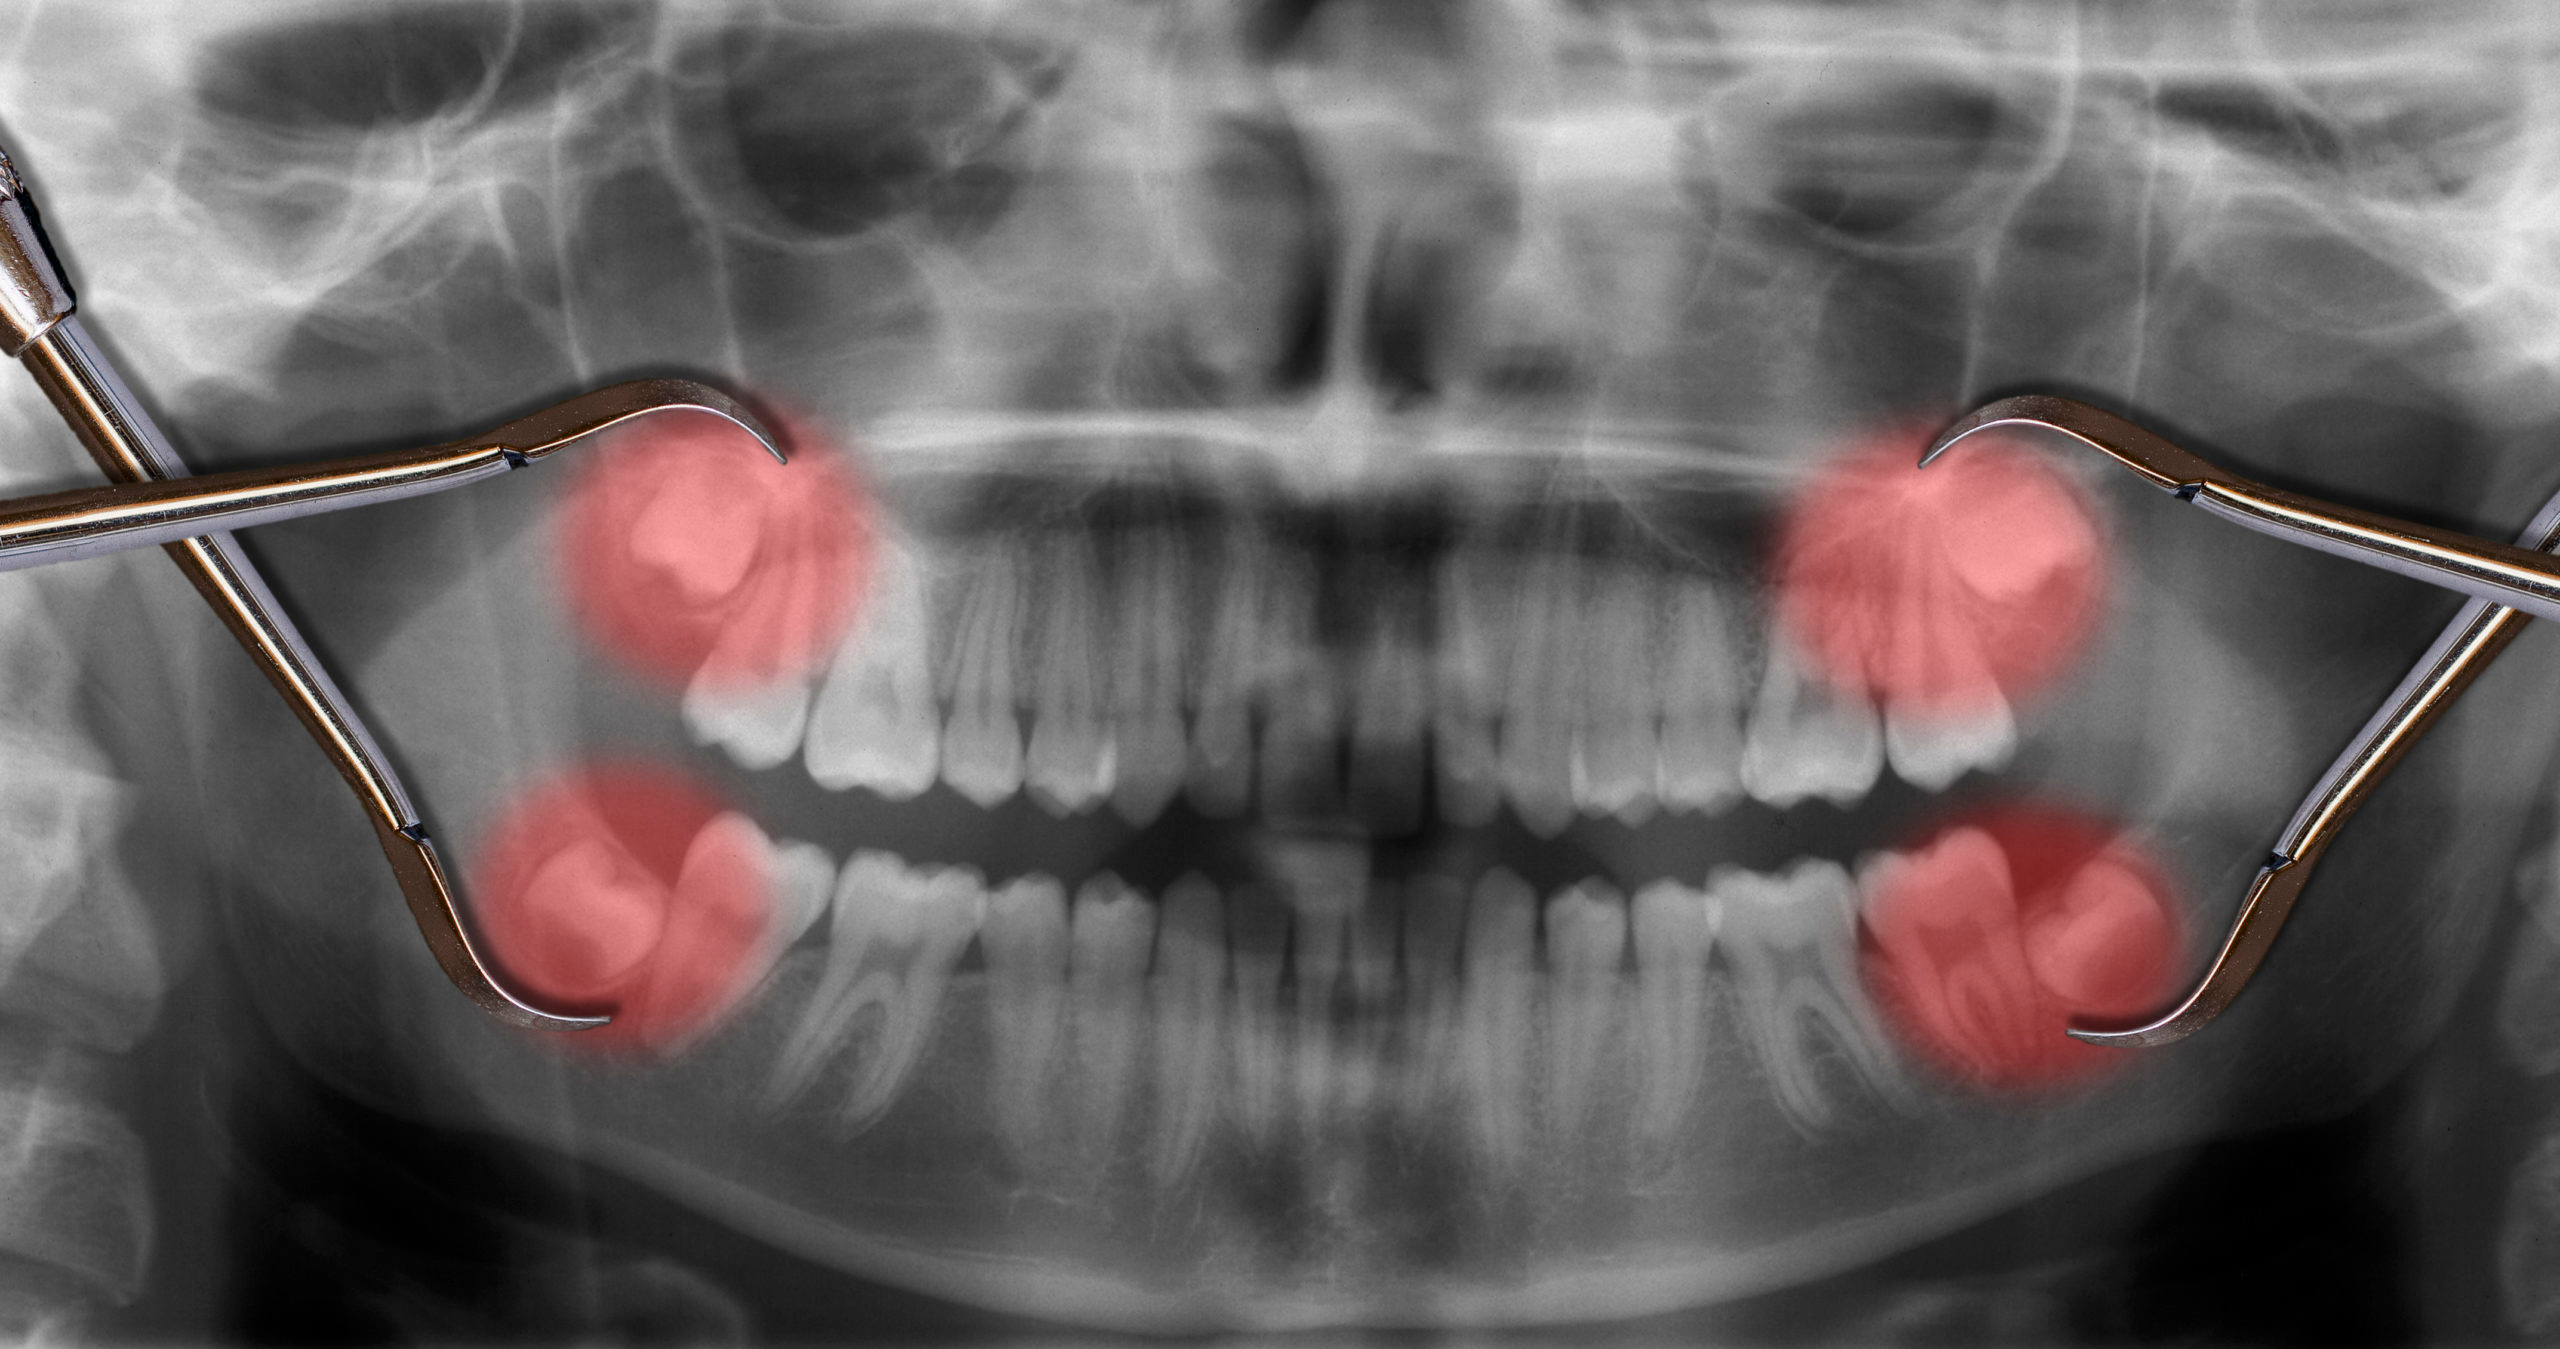

Among the most common issues are overcrowding, where there isn’t sufficient space in the mouth for the wisdom teeth to properly emerge, leading to misalignment of the other teeth. Impaction is another significant concern, where the impacted wisdom teeth fail to fully emerge through the gums, creating potential for pain, infection, and damage to adjacent teeth.

Moreover, the angle at which wisdom teeth grow can sometimes pose problems. They may grow at an angle that disrupts the natural alignment of the dental arch, putting undue pressure on adjacent teeth and the jaw. This can not only lead to discomfort but also complicate oral hygiene practices, increasing the risk of cavities and gum disease in hard-to-reach areas.